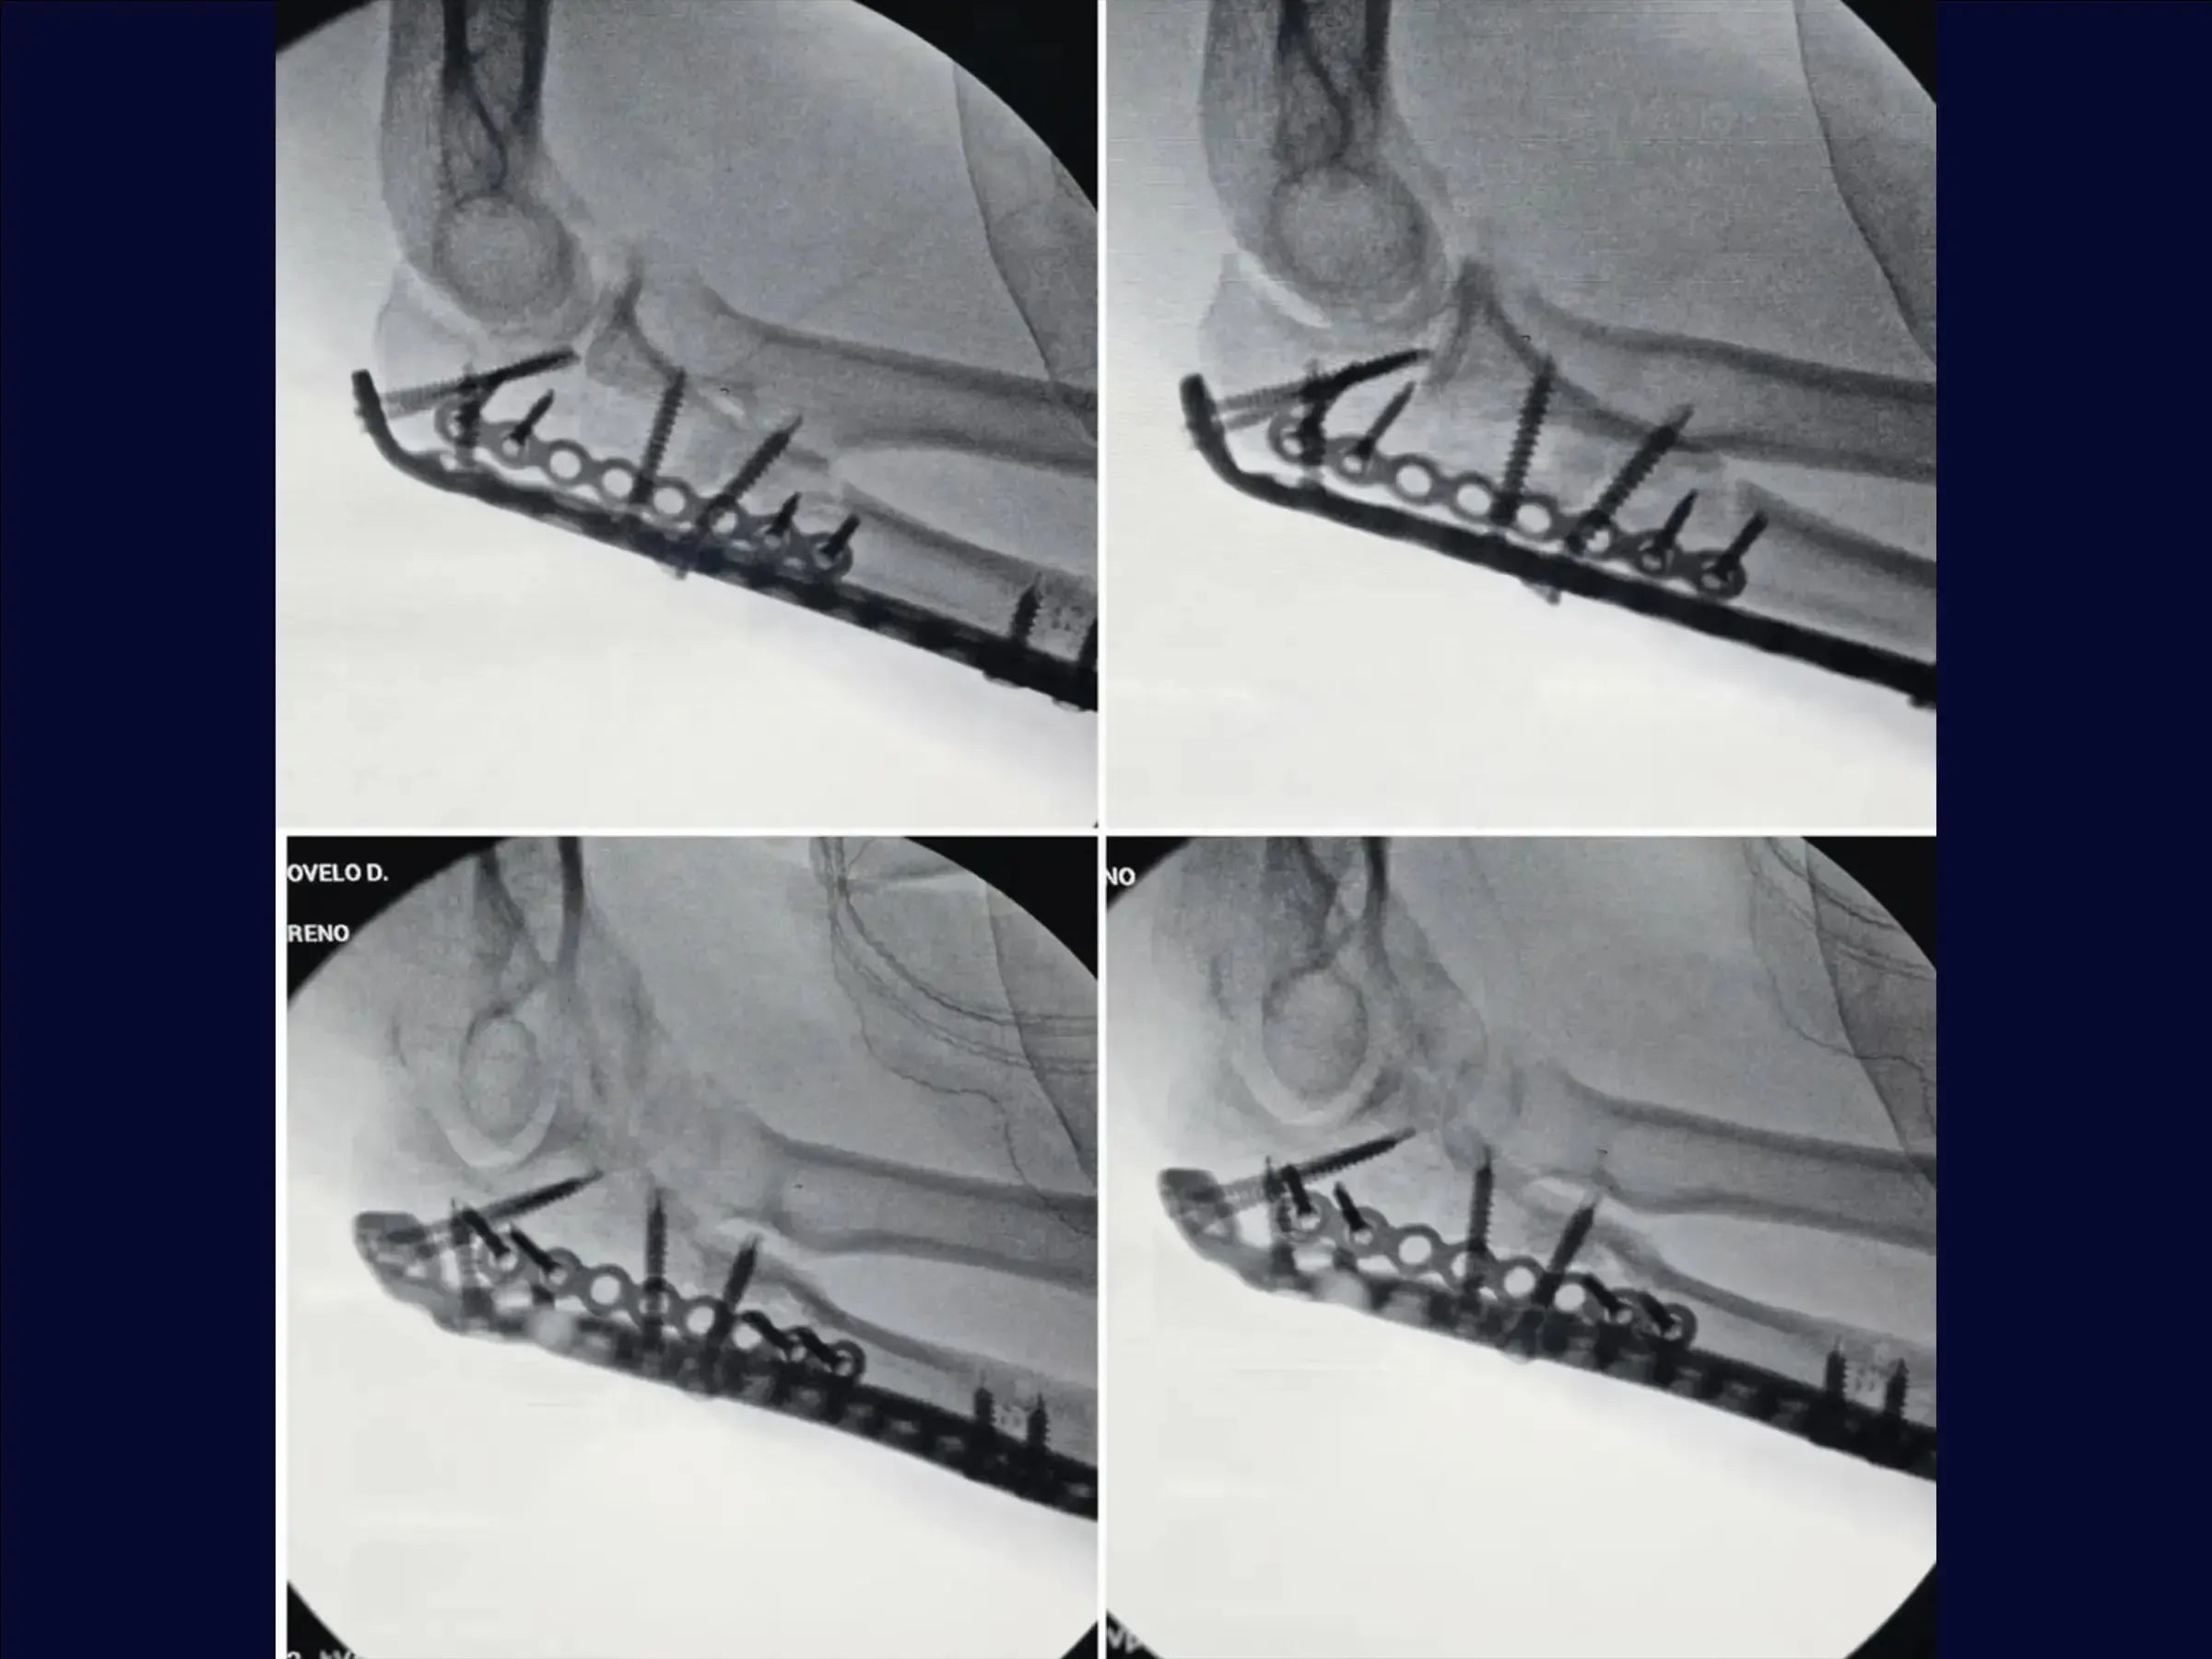

- Reduction of the Ulna: Fracture reduction with Kirschner wires.Lateral fragment fixation with a mini-fragment plate, enabling the use of a long plate on the olecranon.

- Finalization and Stabilization: Pull-out tying and definitive fixation with a long locked plate on the ulna metaphysis, ensuring joint stability.

- Closure and Final Result: Linear opening of the musculature, reconstructed fracture, and congruent joint. Well-distributed screws, with anatomical closure by layers.